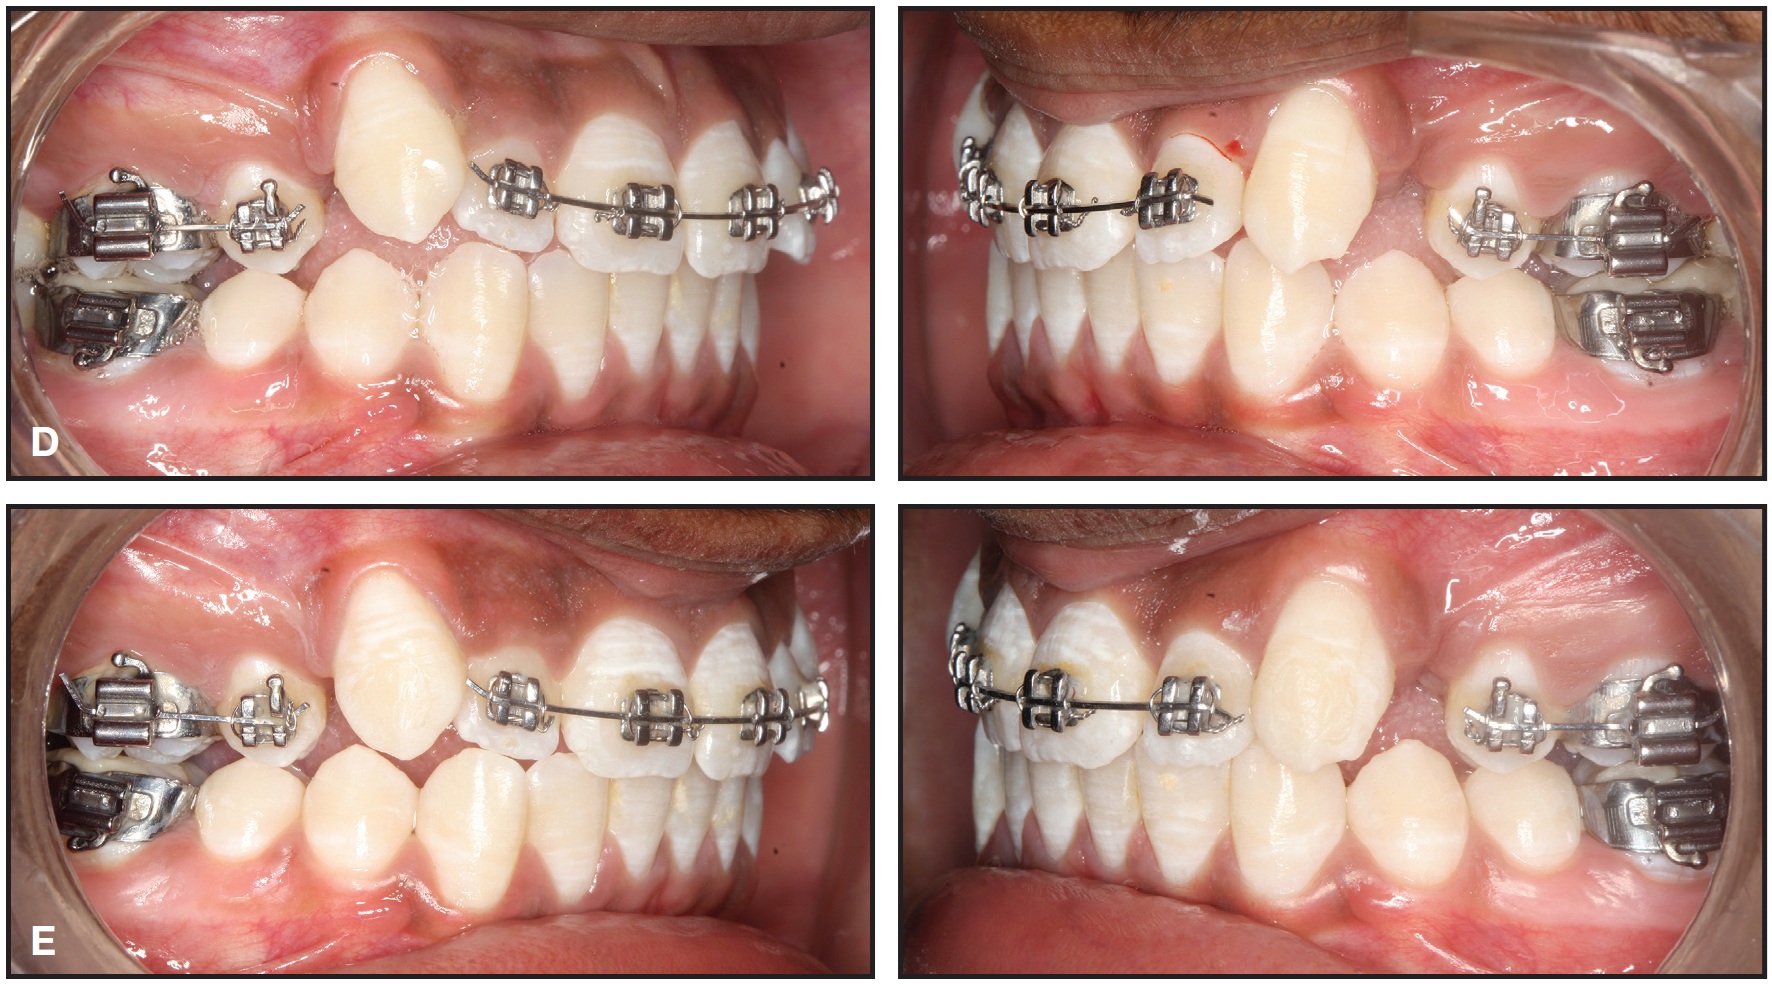

Fig. 2 Case 1. Sequential drifting of canines after one (A), three (B), and five (C) months of treatment with MBT* fixed appliances, transpalatal arch, and nickel titanium archwires.

All teeth except the ectopic canines were bonded. The incisors were aligned with segmental mechanics on .014" and .016" nickel titanium archwires, and the canines were allowed to drift into the extraction spaces without any direct force application (Fig. 2).

Considering the patient’s age, profile, and arch discrepancy, we decided to extract all four first premolars, followed by driftodontics with group A anchorage in both arches. Fixed mechanotherapy would involve .022" MBT* appliances and a transpalatal arch.